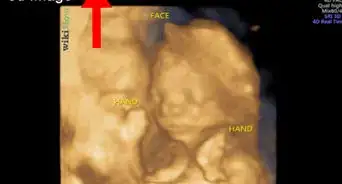

1Skull Theory: Some people believe that baby boys and baby girls have different skull shapes. The basic idea of this theory is that baby boys tend to have bigger, squarish heads, while baby girls have curvier, rounded heads. Unfortunately, there’s really no scientific evidence to support this theory—but it can still be a fun way to “guess” your baby’s sex ahead of time.[1]